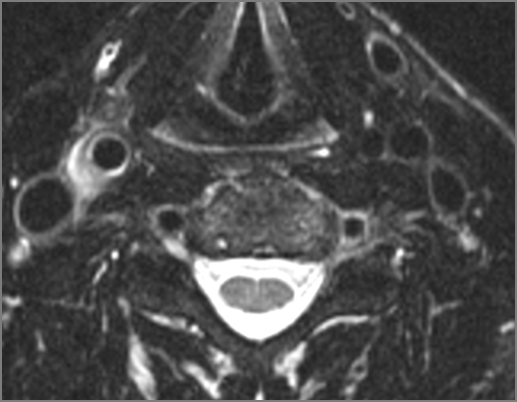

There is edema/abscess within in the prevertebral or paravertebral spaces. |

Yes | NA |

There is erosive process involving the disc spaces or other components of the spine. |

No | NA |

Pharyngitis with suppurative retropharyngeal adenitis.